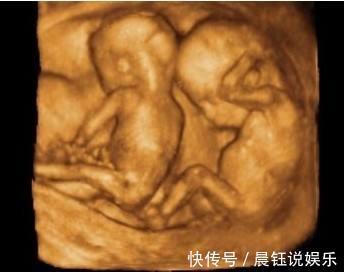

很快的手术就开始了,由于是三胞胎,护士和医生在整个手术的过程中显得十分的小心翼翼,深怕自己一个不小心哪个步骤出错了就会伤害到孕妇和孩子。大约十分钟之后,老大平安降生,接着,老二,老三也相继出生,可当医生把第三个孩子抱出来的时候,却发现圆圆怀的不止三个孩子,还有一个孩子蜷缩在孕妇的体内,这个孩子相比其他三个孩子来说更加的瘦小,这四个孩子还都清一色的都是男孩子。产房外等着的家人听着母子平安都纷纷送了一口气。